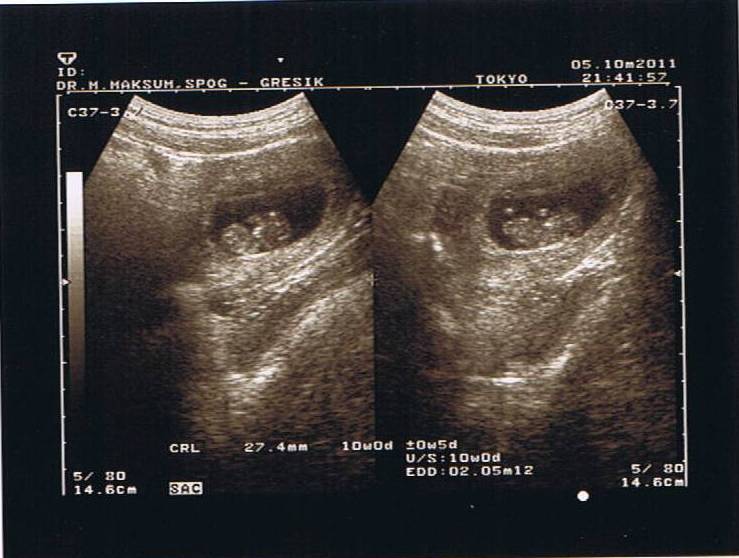

USG 3 months

3 months BADAN, KEPALA DAN KAKI

Amazing, semua terlihat sangat jelas, bahkan tangan dan kakinya terlihat bergerak2, benar benar anugrah Tuhan yang sangat sangat luar biasa.